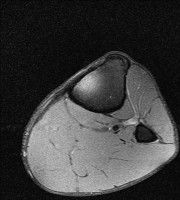

무릎 mri 간단히 봐주실 수 있으시나요 ㅠㅠ

안녕하세요 8년전 십자인대 수술하고 최근 무리한 운동에 무릎 불편감이 생겨서

mri 찍었습니다.

진단결과는 첫 찍은 병원에서 활액막염 이라는 진단을 받았습니다. 혹시 봐주실 수 있으실까요?

올라온 MRI가 단편적이라서 정확한 진단에 어려움이 있지만 십자인대에는 큰 이상이 있지는 않은것 같으며, 무릎관절내 물이 있는 것으로 보아 활액막염의 진단이 맞을 것 같습니다.

하지만 단편적인 영상이기 때문에 촬영병원에서 정확한 판독지 등을 받으시는 것이 좋겠습니다.